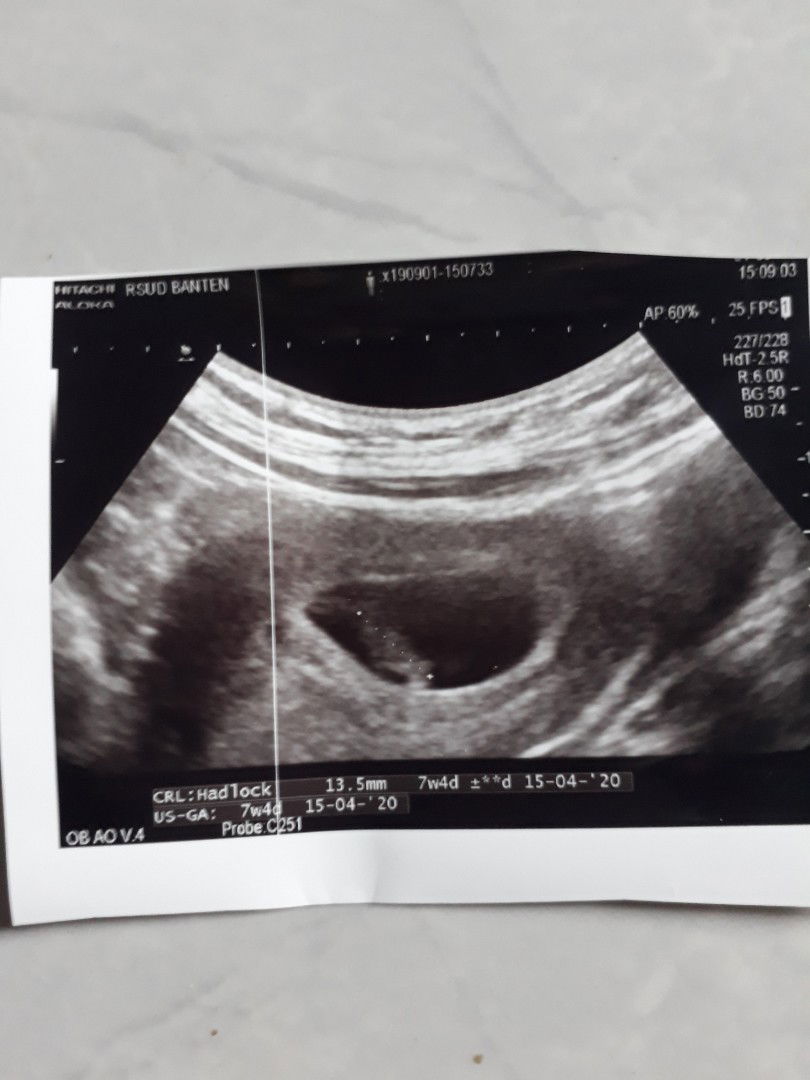

hasil usg 7w4d

Alhamdulillah, sudah terdengar detak jantungnya ? tpi dr. Nyaranin buat bedrest total karena ada nya "ancaman keguguran" ? mohon do'a nya ya para bunda, semoga aku dan baby ttp sehat slalau.. aamiin